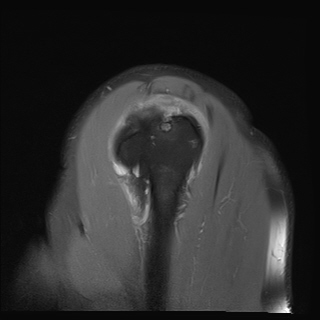

±Ø»ó°Ç³»Ãø Á¾´Ü¸é°Ë»ç¿¡¼­ ±Ø»ê°Ç ºÎÂøºÎÀÇ  ÀÛÀº ÆÄ¿­°ú Á¡¾×³¶ ºÎÁ¾ÀÌ °üÂûµÊ(±×¸² 2, 3).